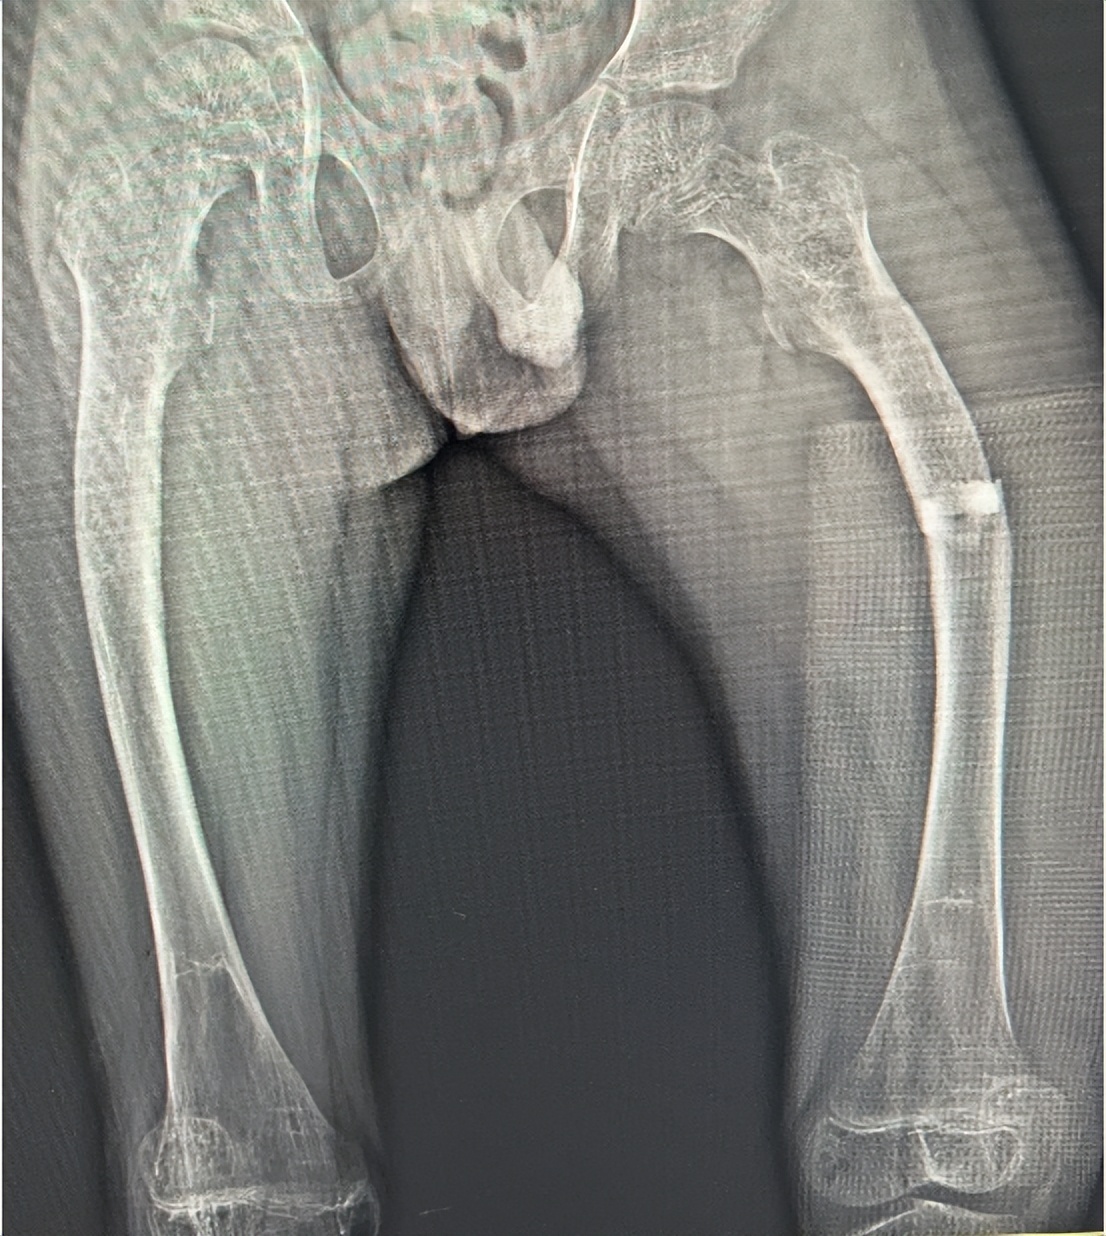

5月6日是国际成骨不全日,旨在让成骨不全症(罕见骨病)儿童被看见、被关注,促进早诊断、早治疗。5月5日,江西省儿童医院接诊一名患有成骨不全症的9岁男童,骨科熊斌团队成功为其进行左侧股骨骨折复位+截骨矫形内固定,右侧股骨多段截骨矫形内固定手术。目前,男童正在康复中。

来自江西抚州的磊磊(化名)在近2年内已出现三次股骨骨折,存在日常行动障碍,4天前磊磊不慎受伤再次骨折,磊磊的父母立即带其前往江西省儿童医院骨科就诊。

磊磊办理入院后,骨科主任熊斌团队通过详细检查,确诊为左侧股骨骨折,成骨不全。根据磊磊的病情,考虑到磊磊两侧大腿因反复受伤已出现畸形改变,熊斌、副主任医师林智峰、主治医师江琦庆进行多次讨论及风险评估后制定了详细的手术方案,决定采用可延长髓内钉为内固定,为磊磊进行左侧股骨骨折复位+截骨矫形内固定,右侧股骨多段截骨矫形内固定治疗。熊斌团队在手术室麻醉科及护理团队的默契配合下,顺利为磊磊实施手术,历时8小时。目前,磊磊正在康复中。